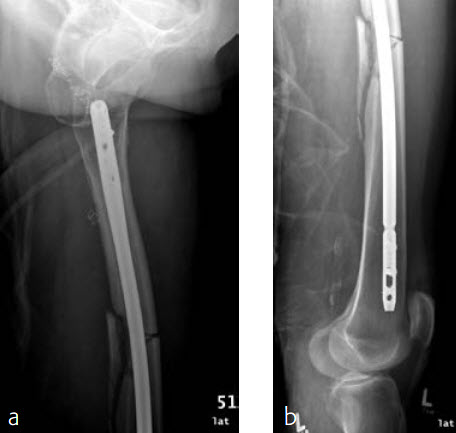

Case 2: Left femur fracture

A 70-year-old female patient suffered an AO 32-B3 fracture of the left femur (Figs 3 and 4). Fixation with the FRNA for a tip of the trochanter entry point (nail diameter 10 mm; nail length 400 mm; reaming to 12 mm) in standard interlocking mode (Figs 5 and 6). Proximal locking with antegrade and transverse dynamic locking positions. Distal locking with two lateral to medial locking screws in static locking position.